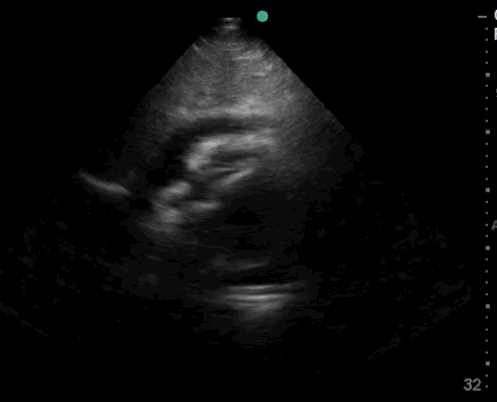

11_Heart_A4CH

Bad Image

11_Heart_A4CH – Bad Image